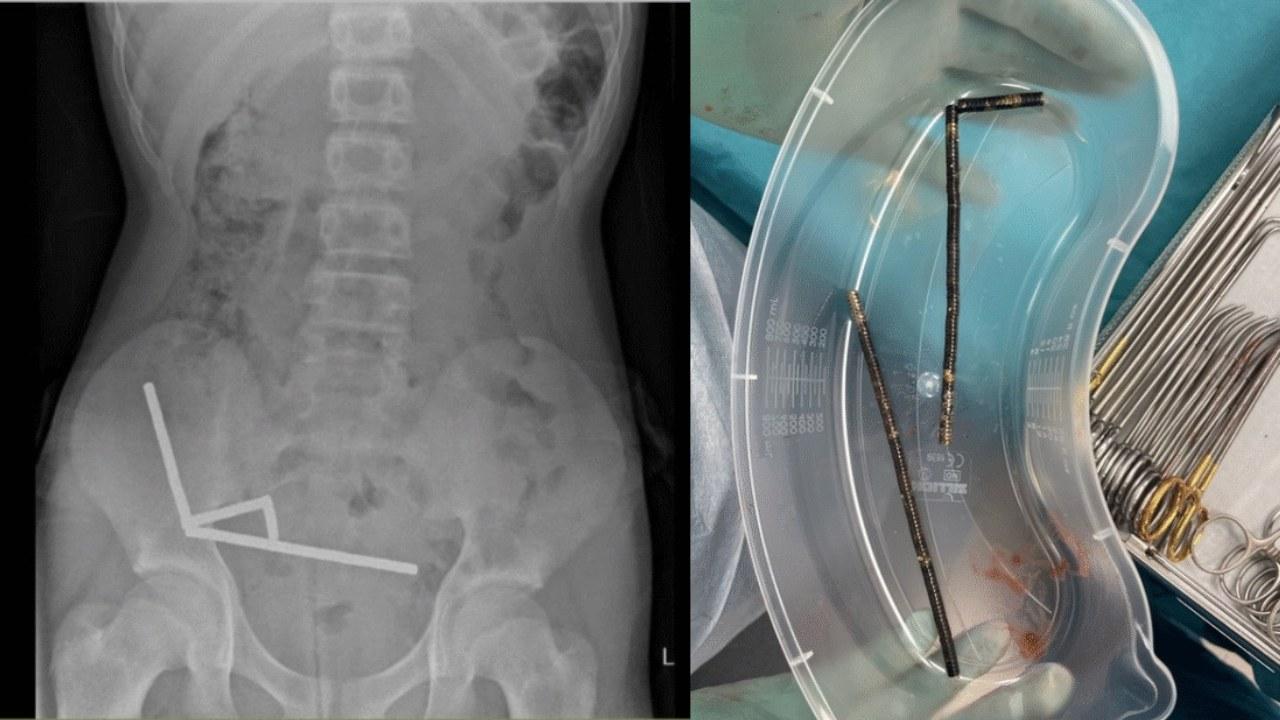

離奇事件發生在新西蘭北島,一名13歲男童因劇烈腹痛被送到醫院,他告訴醫生自己一周前吞下了100多顆磁鐵,但後來取出了近200顆小磁鐵。男童稱這些磁鐵是他在購物網站天貓買入。

X光中顯示,這些小磁鐵在他腸子裡的不同部位中形成4條鏈子互相拉扯,並切斷了附近組織的血流,壓力更導致多處壞死。

醫生為他移除磁鐵和部分受損腸道,男童最終在醫院裡住了8天。